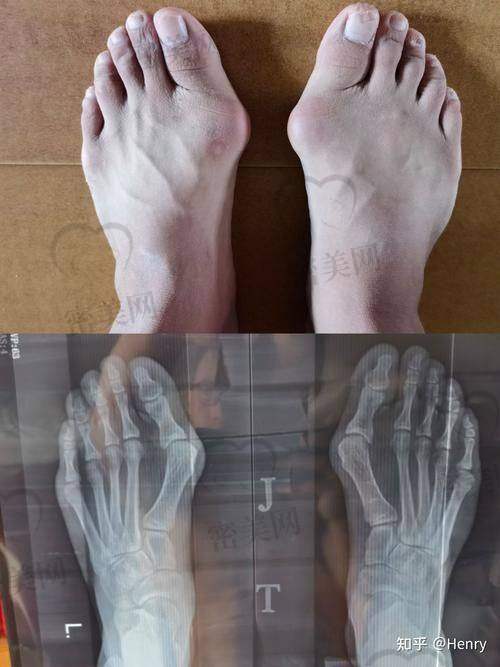

拇外翻,又叫“大脚骨”,让无数人又痛又烦,不仅走起路来难受,还穿不了喜欢的鞋,影响美观不说,长时间还会造成其他并发症。想手术却又担心“踩坑”?其实,如果你知道温建民医生是谁,就知道选他基本不会失望。微创技术高成功几率,术后修复快,是特别多人治愈拇外翻的关键一步。我们来从多个角度看看为什么拇外翻手术选温建民医生真的不容易踩坑!

1. 补齐术前检查:拍X光/CT,结合步态分析确定病变程度;